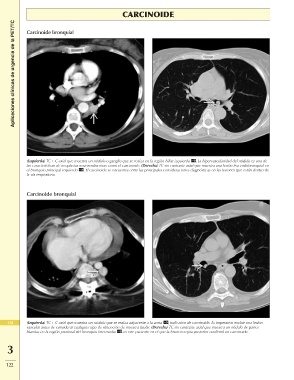

Aplicaciones clínicas de urgencia de la PET/TC Carcinoide bronquial

(Izquierda) TC + C axial que muestra un nódulo o ganglio que se realza en la región hiliar izquierda . La hipervascularidad del nódulo es una de

las características de neoplasias neuroendocrinas como el carcinoide. (Derecha) TC sin contraste axial que muestra una lesión lisa endobronquial en

el bronquio principal izquierdo . El carcinoide se encuentra entre las principales consideraciones diagnósticas en las lesiones que están dentro de

la vía respiratoria.

Carcinoide bronquial

418 (Izquierda) TC + C axial que muestra un nódulo que se realza adyacente a la aorta , indicativo de carcinoide. Es imperativo excluir una lesión

vascular antes de considerar cualquier tipo de obtención de muestra tisular. (Derecha) TC sin contraste axial que muestra un nódulo de partes

blandas en la región proximal del bronquio intermedio en este paciente en el que la broncoscopia posterior confirmó un carcinoide.